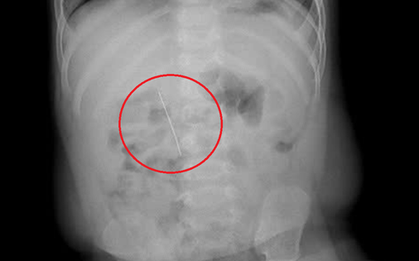

Bé gái 3 tuổi bị sốt cao, ho nhiều, được chẩn đoán viêm phổi và nằm viện gần 30 ngày nhưng tình trạng không thuyên giảm. Trong quá trình siêu âm, bác sĩ phát hiện ổ bụng trẻ có khối lạ nghi dị vật, lập tức chuyển bệnh nhi đến Bệnh viện Nhi đồng 2.